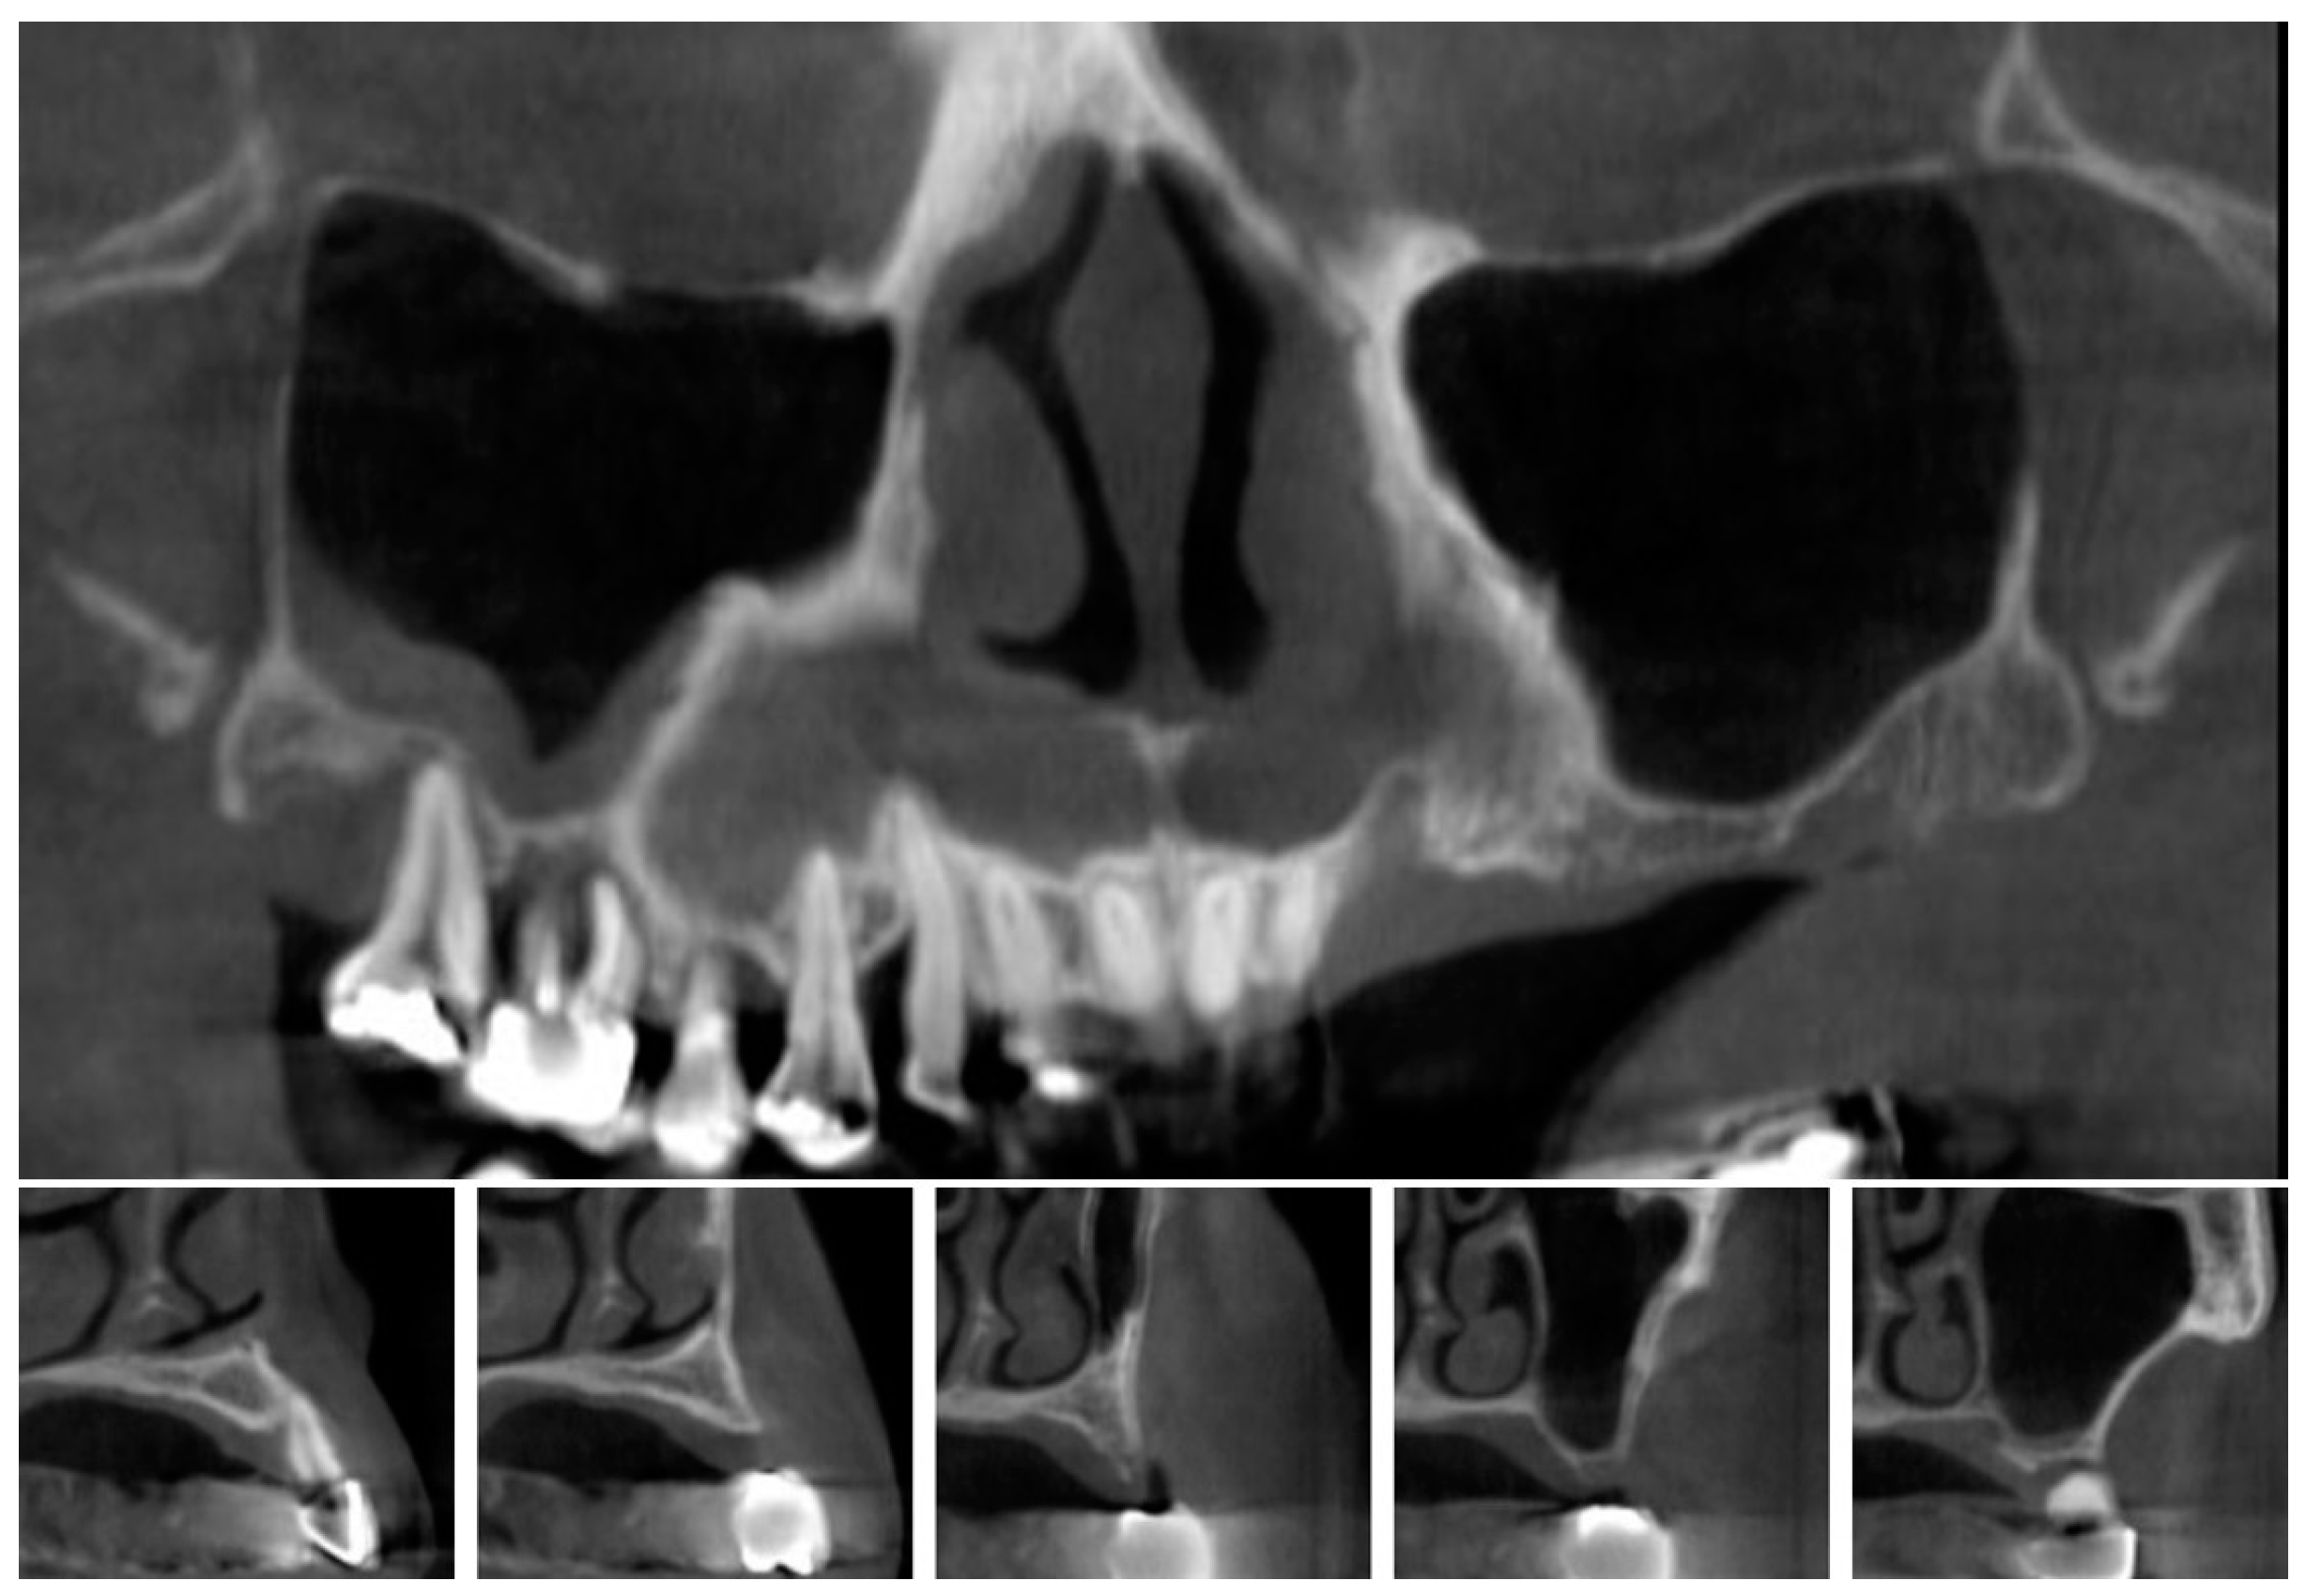

| 1 | #16 | 5 | 12 | 18 | 14 | 9 |

| 2 | #26 | 3 | 18 | 17 | 13 | 10 |

| 3 | #27 | 5 | 16 | 16 | 14 | 9 |

| 4 | #14,15,16,17 | 5,3,5,5 | 22 | 15,18,14,16 | 15,16,14,14 | 10,13,9,8 |

| 5 | #26,27 | 4,4 | 16 | 16,16 | 15,12 | 11,8 |

| 6 | #26 | 6 | 16 | 18 | 20 | 14 |

| 7 | #17 | 2 | 24 | 16 | 15 | 13 |

| 8 | #27 | 2 | 22 | 19 | 18 | 16 |

| 9 | #16 | 2 | 22 | 16 | 14 | 12 |

| 10 | #16,26 | 3,3 | 23 | 23,20 | 20,22 | 17,19 |

| 11 | #26,27 | 3,2 | 24 | 19,18 | 20,16 | 17,14 |

| 12 | #27 | 4 | 22 | 16 | 15 | 11 |

| 13 | #16 | 5 | 12 | 14 | 14 | 9 |

| 14 | #26 | 4 | 16 | 12 | 12 | 8 |

| 15 | #16 | 1 | 20 | 22 | 18 | 17 |

| 16 | #17 | 5 | 13 | 17 | 20 | 15 |

| 17 | #26,27 | 6,6 | 15 | 10,11 | 15,16 | 9,10 |

| 18 | #27 | 3 | 25 | 12 | 14 | 11 |

| 19 | #26,27 | 1,2 | 20 | 21 | 14,14 | 13,12 |